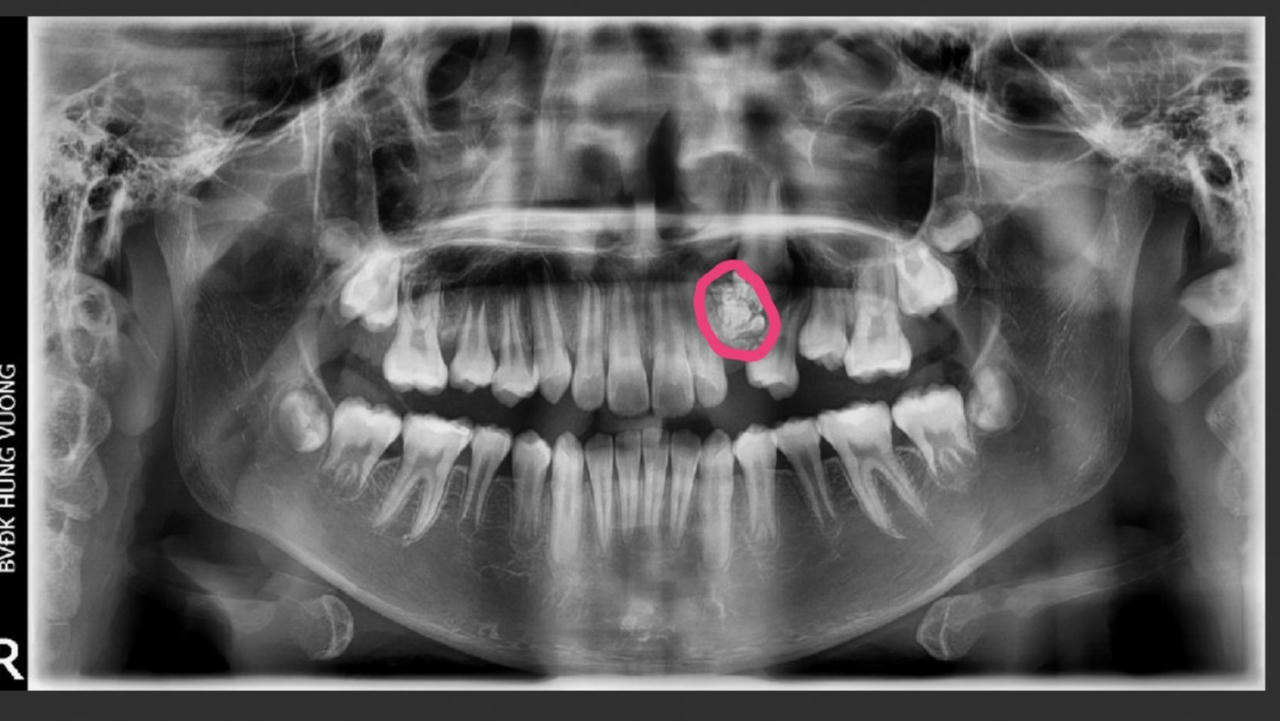

Được biết, bệnh nhân được gia đình đưa đến bệnh viện khám với lý do 12 tuổi nhưng răng nanh hàm trên bên trái vẫn chưa mọc. Kết quả chụp răng toàn cảnh của bệnh nhân cho thấy hình ảnh khối u răng kết hợp vị trí hàm trên bên trái.

Ngay lập tức, bệnh nhân được chỉ định phẫu thuật loại bỏ khối u răng. Trong quá trình phẫu thuật, các bác sĩ lấy ra gần 20 chiếc răng nhỏ tại khối u có đầy đủ thân, tủy và chân răng. Sau đó, bác sĩ đã thực hiện đặt khí cụ kéo răng nanh ngầm về đúng vị trí.